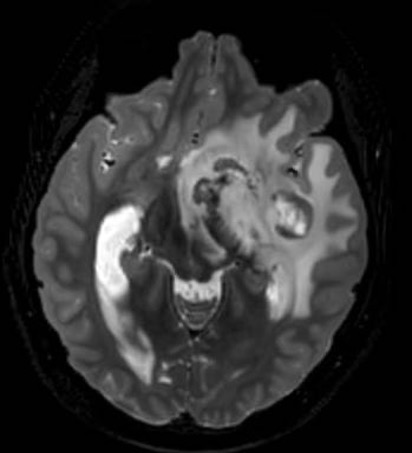

21 y/M 2018 - headache, LOW, low grade fever.Imaging had seller mass lesion for which referred to higher centre (didn't follow up). 2020 - Additiona